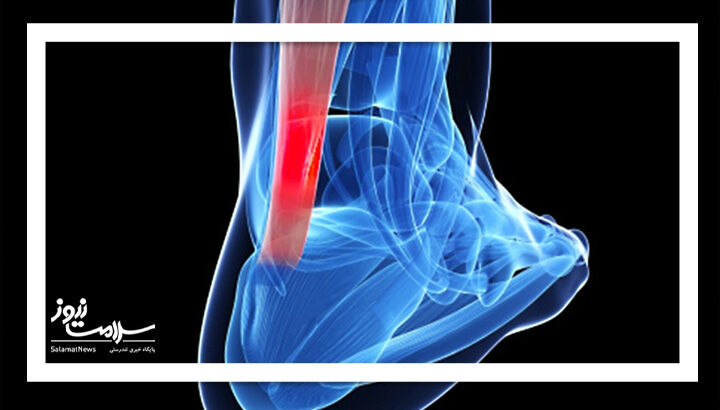

مشکلات تاندون آشیل

تاندون آشیل عضلات ساق پا را به پاشنه متصل میکند و تکرار حرکتها میتواند باعث التهاب آن شود. در موارد جدی، ممکن است این تاندون پاره شود که نیاز به استراحت و در بعضی موارد جراحی دارد.